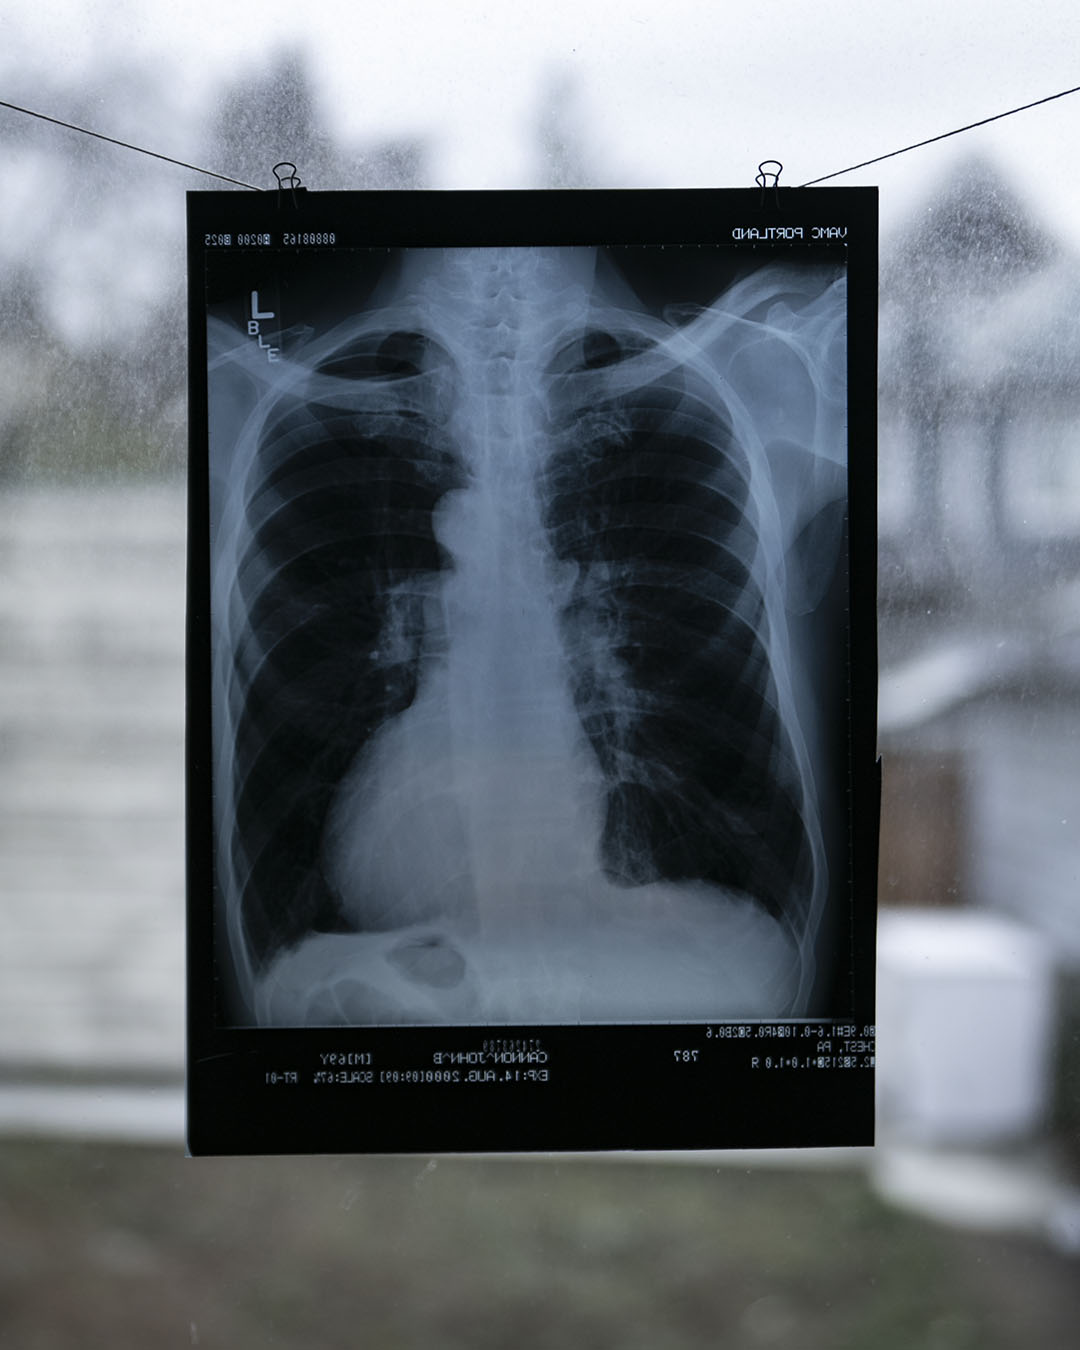

Vintage Chest X-Ray

Vintage Chest X-Ray

Amazing vintage x-rays, price is for one and the one you receive may differ from the examples photographed. There is about 20 available, sourced from the US. All unique and in good condition. Approx 35x28cm